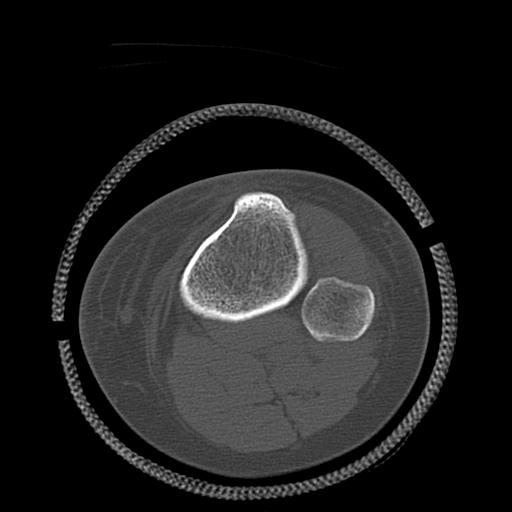

49554 3/13 膝 4R 3/16 4R 1/18 2R 78歳男性 膝蓋骨骨折